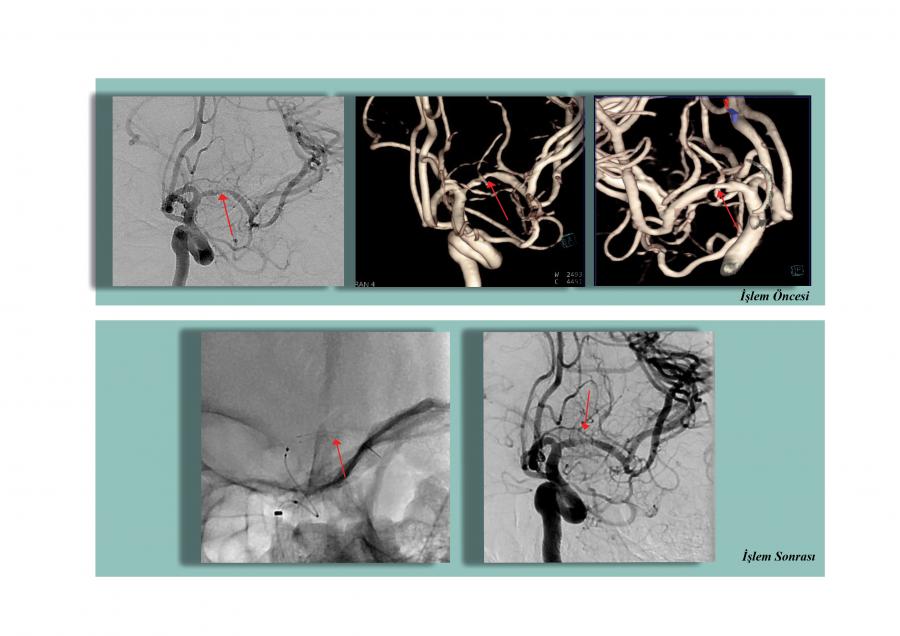

48 yaşındaki diğer hastamızın ilk incelemelerinde beyin kanaması bulgularına rastlandı. Çekilen Beyin Damarları Anjiyografisinde, 8 mm çapında baloncuk (anevrizma) tespit edildi. Patlaması an meselesi olan anevrizmaya kapalı yöntemle kasık atar damarından girildi. Sağ ve sol arka beyin damarını korumak için stent yerleştirildi. Bu aşamadan sonra kritik olan anevrizma koil (tel yumak) ile kapatıldı. Zorlu geçen bu girişimsel işlemler, hastamızın büyük ve riskli bir ameliyata gerek kalmadan şikayetlerini ortadan kaldırıp kısa bir sürede şifa ile taburcu olmasını sağladı.

2. Endovasküler Anevrizma Tedavileri (Koil- Stent-Sıvı Ajanlar ile)